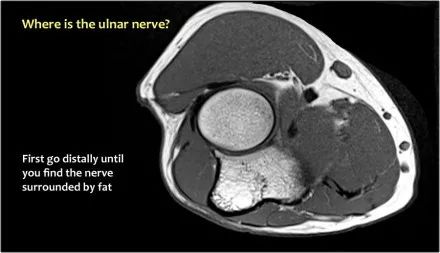

因此,当我们回到图像时,您会发现很难找到神经。任何这些皮下结构都可以是转位神经。一种方法是远端跟随结构,直到你发现远端的尺神经位于由脂肪包围的前臂近端的正常位置。然后当你向近端跟随它时,你会发现这是皮下移位。